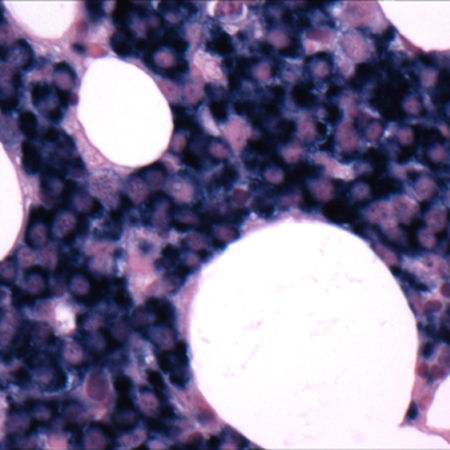

A imuno-histoquímica e a citometria de fluxo podem ser realizadas em amostras de medula óssea para confirmar a presença de plasmócitos monoclonais e quantificar com precisão o envolvimento dos plasmócitos.[45]National Comprehensive Cancer Network. NCCN clinical practice guidelines in oncology: multiple myeloma [internet publication].

[Figure caption and citation for the preceding image starts]: Biópsia da medula ósseaCortesia do Dr. Robert Hasserjian, Hematopatologia, Massachusetts General Hospital; usado com permissão [Citation ends].

[Figure caption and citation for the preceding image starts]: Biópsia da medula óssea após análise histoquímica de cadeia leve kappaCortesia do Dr. Robert Hasserjian, Hematopatologia, Massachusetts General Hospital; usado com permissão [Citation ends].

[Figure caption and citation for the preceding image starts]: Biópsia da medula óssea após análise histoquímica de cadeia leve lambdaCortesia do Dr. Robert Hasserjian, Hematopatologia, Massachusetts General Hospital; usado com permissão [Citation ends].

[Figure caption and citation for the preceding image starts]: Aspirado mostrando infiltrado plasmocitárioCortesia do Dr. Robert Hasserjian, Hematopatologia, Massachusetts General Hospital; usado com permissão [Citation ends].